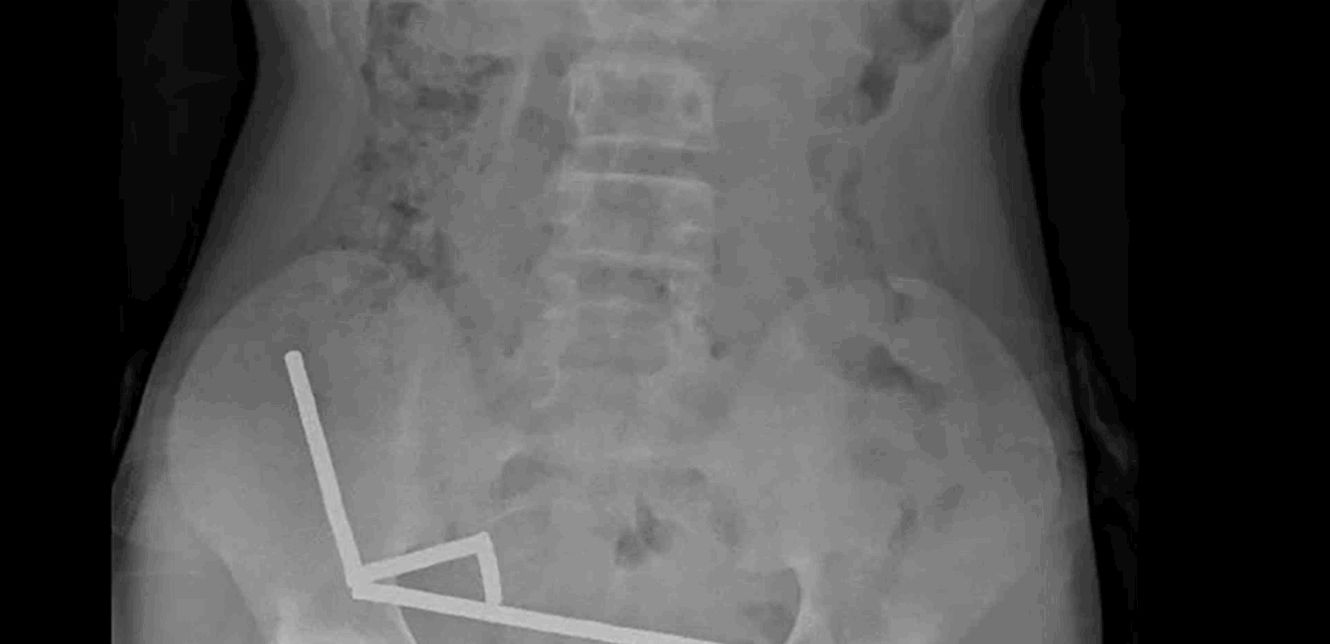

أظهرت صور الأشعة تجمع المغناطيسات في أربعة خطوط داخل الأمعاء "ملتصقة ببعضها بسبب القوى المغناطيسية"، ما سبّب تلفًا في الأنسجة.